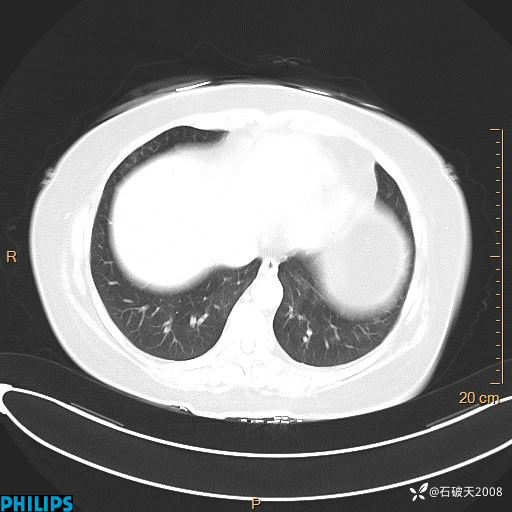

肺结节病?纵膈型肺癌?淋巴瘤?有点意思,欢迎围观

女 52岁 主 诉:咳嗽10余天,咳痰2天。

现病史:10余天前无明显诱因出现咳嗽,呈阵发性干咳,伴咽喉部发痒,无咽痛,无咳痰,无鼻塞、流涕、打喷嚏,无发热、畏寒、寒颤,无头痛、头晕,无胸闷、胸痛,无反酸、烧心,无腹痛、腹泻,无尿频、尿急,无皮疹等,在当地诊所求治,给予口服药物治疗(具体不详),病情无好转。遂在当地社区卫生服务中心开具口服药物治疗(具体不详),疗效欠佳。2天前出现咳痰,在我院门诊求治,行胸部CT提示肺部感染,建议住院,患者要求口服药物治疗,目前仍咳嗽、咳白色粘痰,白天量多,夜间自觉喉部喘鸣音,遂再次来院就诊,以“肺部感染”为诊断收入院。发病以来,神志清,精神可,饮食可,夜间睡眠差,大小便正常,近期体重无明显变化。

纵隔窗